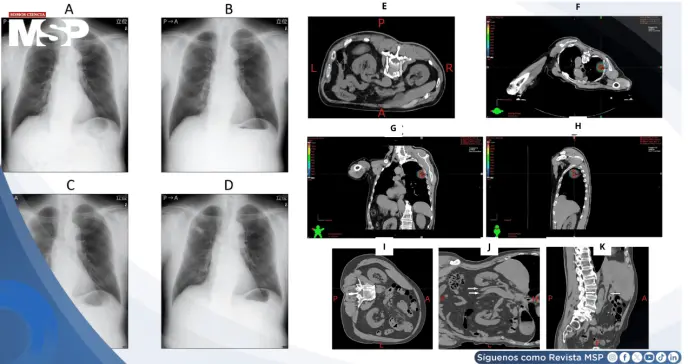

Durante la tomografía computarizada cuatridimensional (4D-CT) —usada para medir el movimiento respiratorio del tumor—, el paciente desarrolló súbitamente sudoración intensa, náuseas y vómitos, lo que obligó a suspender el procedimiento.

Las imágenes mostraron una vena cava inferior comprimida entre el riñón derecho y una aorta abdominal tortuosa, sin evidencia de masas o tumores retroperitoneales. Esta disposición anatómica explicaba el pinzamiento dinámico de la VCI al adoptar ciertas posiciones, reduciendo el retorno venoso y desencadenando síntomas de hipotensión.

Este patrón contrasta con la compresión de la VCI típica del embarazo, donde la posición lateral izquierda suele aliviar la obstrucción; en este caso, la posición lateral izquierda la exacerbaba, debido a la orientación anómala de los órganos abdominales.

Ante la imposibilidad de realizar el tratamiento en posición supina, el equipo de radioterapia modificó la técnica de SBRT, eligiendo la posición prona con inclinación lateral derecha, que evitaba la compresión.